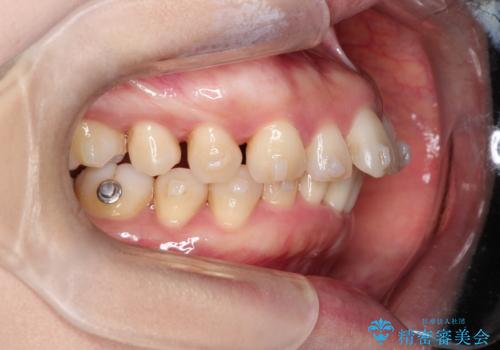

- 矯正装置

- インビザライン

- 前歯が出ていることを主訴に来院されました。

インビザラインにて臼歯部の遠心移動及びIPRを行なっています。

叢生量が多いケースでしたが、綺麗な歯並びとなり患者様にも満足していただきました。